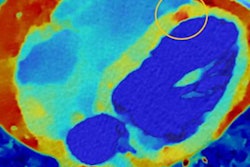

SmartCT produces CT-like 3D images that support diagnosis of disease, therapy planning, and treatment follow-up for interventional radiology procedures. It consists of a touch-screen tablet and can be used for angiography, neurology, soft-tissue imaging, and guidewire/catheter navigation, the company said.

SmartCT includes a table-side touchscreen control that offers interventionalists enhanced diagnostic confidence and streamlined workflows. Image courtesy of Philips Healthcare.SmartCT guides users through the process of image acquisition, and clinicians can review and interact with images using a table-side touchscreen module and 3D visualization and measurement tools. The tools include features like distance measurements on 3D images, the ability to remove structures obstructing regions of interest, and the ability to select and store optimum projection angles for recall during procedures.